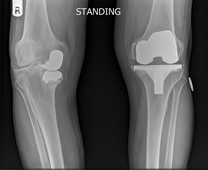

Knee replacement involves replacing the worn out knee joint. The end of the femur is resurfaced with a metallic component, a tray is placed on the tibia and a polyethylene spacer is inserted between the two components. For most total knee replacement the under surface of the kneecap is re-surfaced with a small polyethylene button.

After successful knee replacement we hope to achieve pain relief, a stable straight leg that bend well and will last a long time.

The results for knee replacement are improving enormously, but sadly there are still a number of patients who don’t achieve the good results we are looking for and a small percentage will continue to have ongoing knee pain despite a well performed operation and normal x-rays.